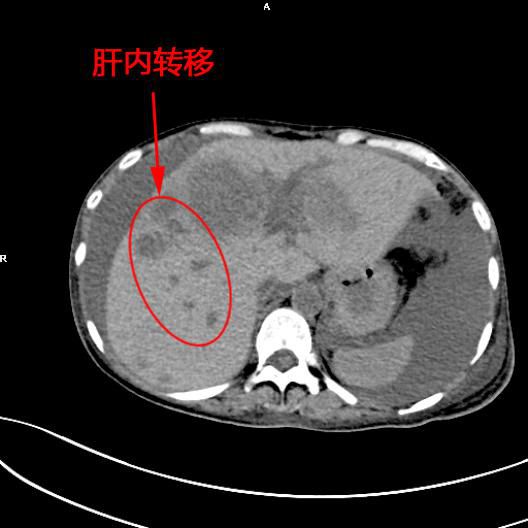

患者陳女士,57歲,汕頭潮南人,2個月前出現右上腹痛,在汕頭大型三甲醫院确診爲膽囊癌,因腫瘤爲晚期,已擴散至肝髒、十二指腸,患者放棄在汕頭治療,回家後自行采用中藥治療。近期右上腹痛加重,反複排黑便,遂來我院住院,診斷爲膽囊癌伴活動性出血。

5月11日下午,内三科主任李旭丹、影像科副主任胡志華上台施術。通過粵東領先的飛利浦DSA造影顯示,患者腫瘤供血血管豐富,膽囊動脈造影可見腫瘤染色明顯,有造影劑外溢,提示部分血管末梢有破裂出血現象,探查胃十二指腸動脈及腸系膜上動脈未見出血征像,豐富的血供使腫瘤能獲取大量的營養快速生長,血管末梢的破裂出血導緻患者反複黑便。